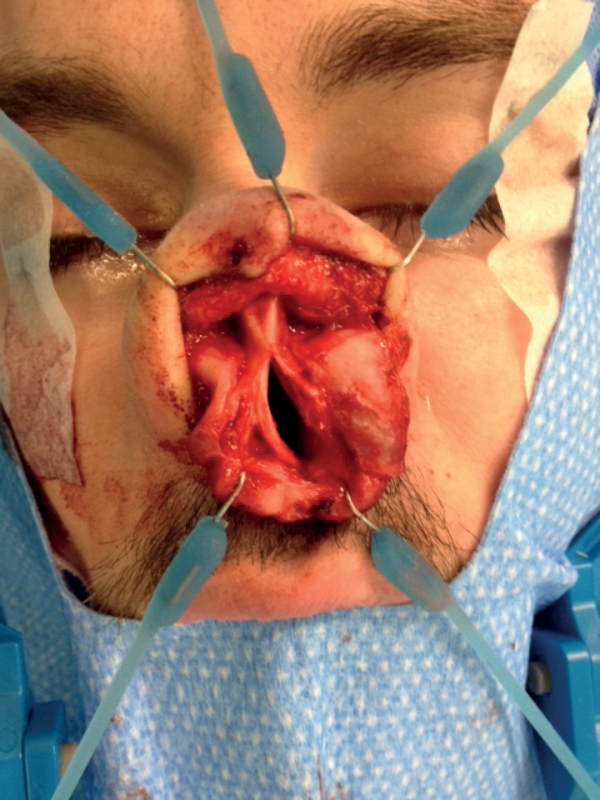

A thorough endoscopic examination of the nose is done to remove any synechae or reduce hypertrophied inferior turbinates to allow access. The size of the perforation is assessed (Figure 1).

Figure 1: Medium sized septal perforation.